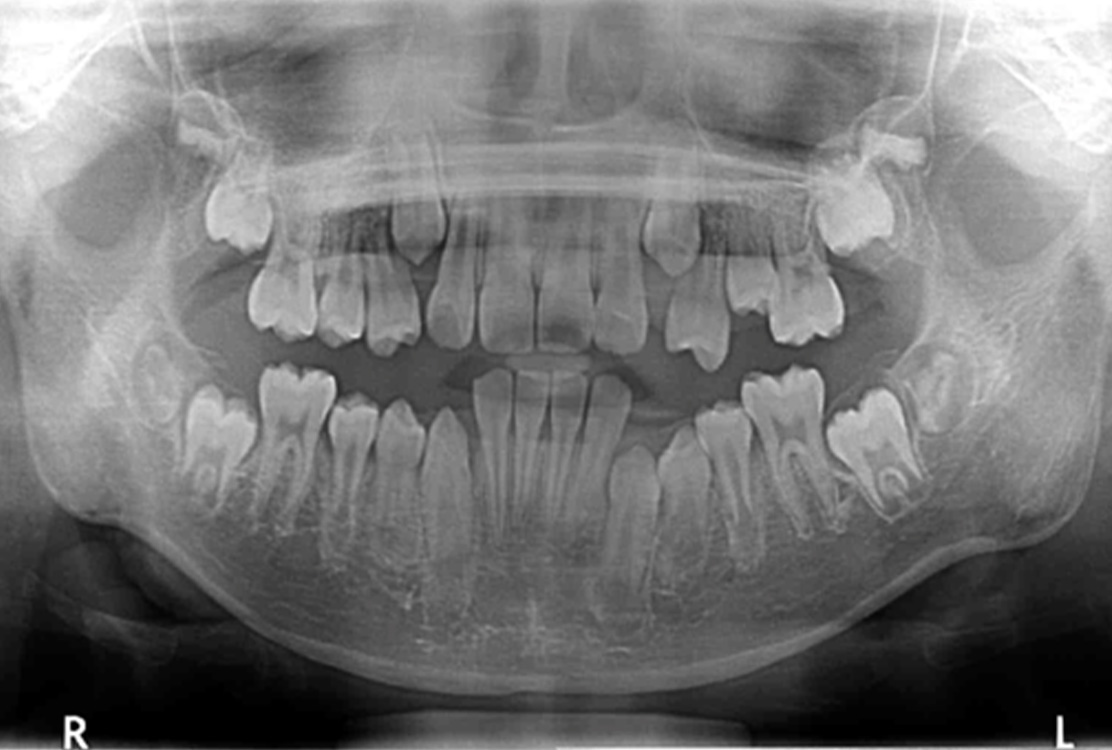

レントゲン画像

治療前